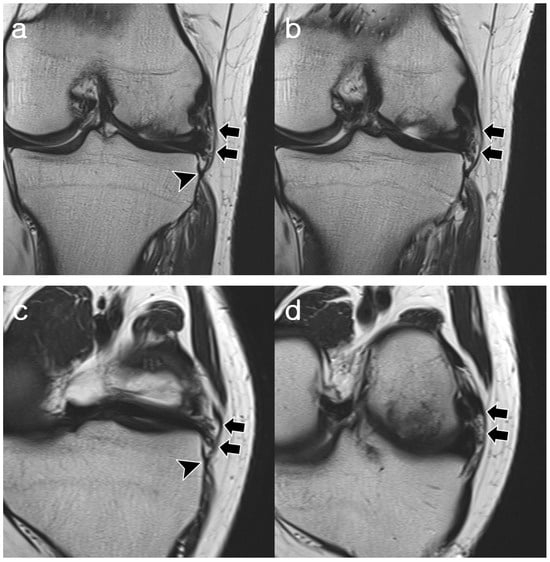

3.2. ALL Visibility

3.3. ALL Morphology